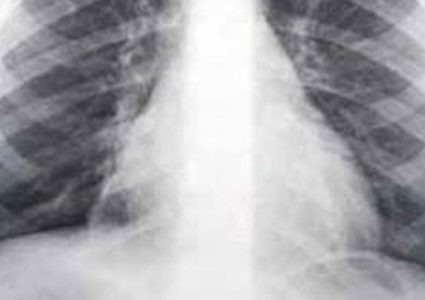

أصيب شاب أمريكي يدعى سكوت دوناهو (49 سنة) بمرض بدأ في شهر مارس الماضي بعدما اصبح يعاني من نوبات سعال شديد، أصبحت لاحقا تنتهي بالتقيؤ. اعتقد الأطباء ...